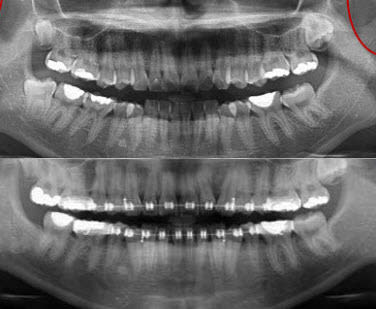

Et même, observez bien les deux panos l'une au dessus de l'autre ainsi les deux télés que j'ai superposées (par la technique des calques à demi transparents sur PSP). Vous verrez alors :

1 que sur les panos la différence de position des condyles n'est vraiment pas flagrante (c'est le moins qu'on puisse dire) !

2 que sur les télés il n'y a pas de remontée postérieure ni de recul de la mandibule comme ce serait la cas si effectivement il y avait eu repositionnement condylien, mais une simple ouverture mandibulaire.

Pour une fois je ne suis pas tout à fait d'accord avec toi. La superposition des deux radios ne montre pas grande chose quand on sait qu'on est en train de parler sur des dixièmes de millimètre ! Par contre on voit une classe I molaire sur la première radio et une classe II presque complète sur la deuxième et je ne crois pas qu'une minime rotation postérieure puisse "reculer" la mandibule et la molaire inférieure autant! Je crois bien que les deux problèmes coexistent à savoir: un repositionnement postérieure de la mandibule avec une rotation postérieure due à l'egression des deuxièmes molaires et l'apparition de points de prématurité .

D'autre part je ne sais pas combien de temps il y à entre les deux radios, Seepan parle de qqs mois mais je vois qu'une troisième molaire a disparu avec une bonne cicatrisation!!?